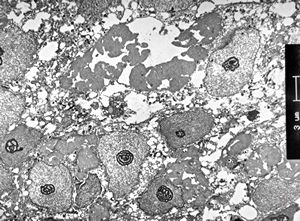

M,66y. | follicular cyst with hyaline Rushton bodies